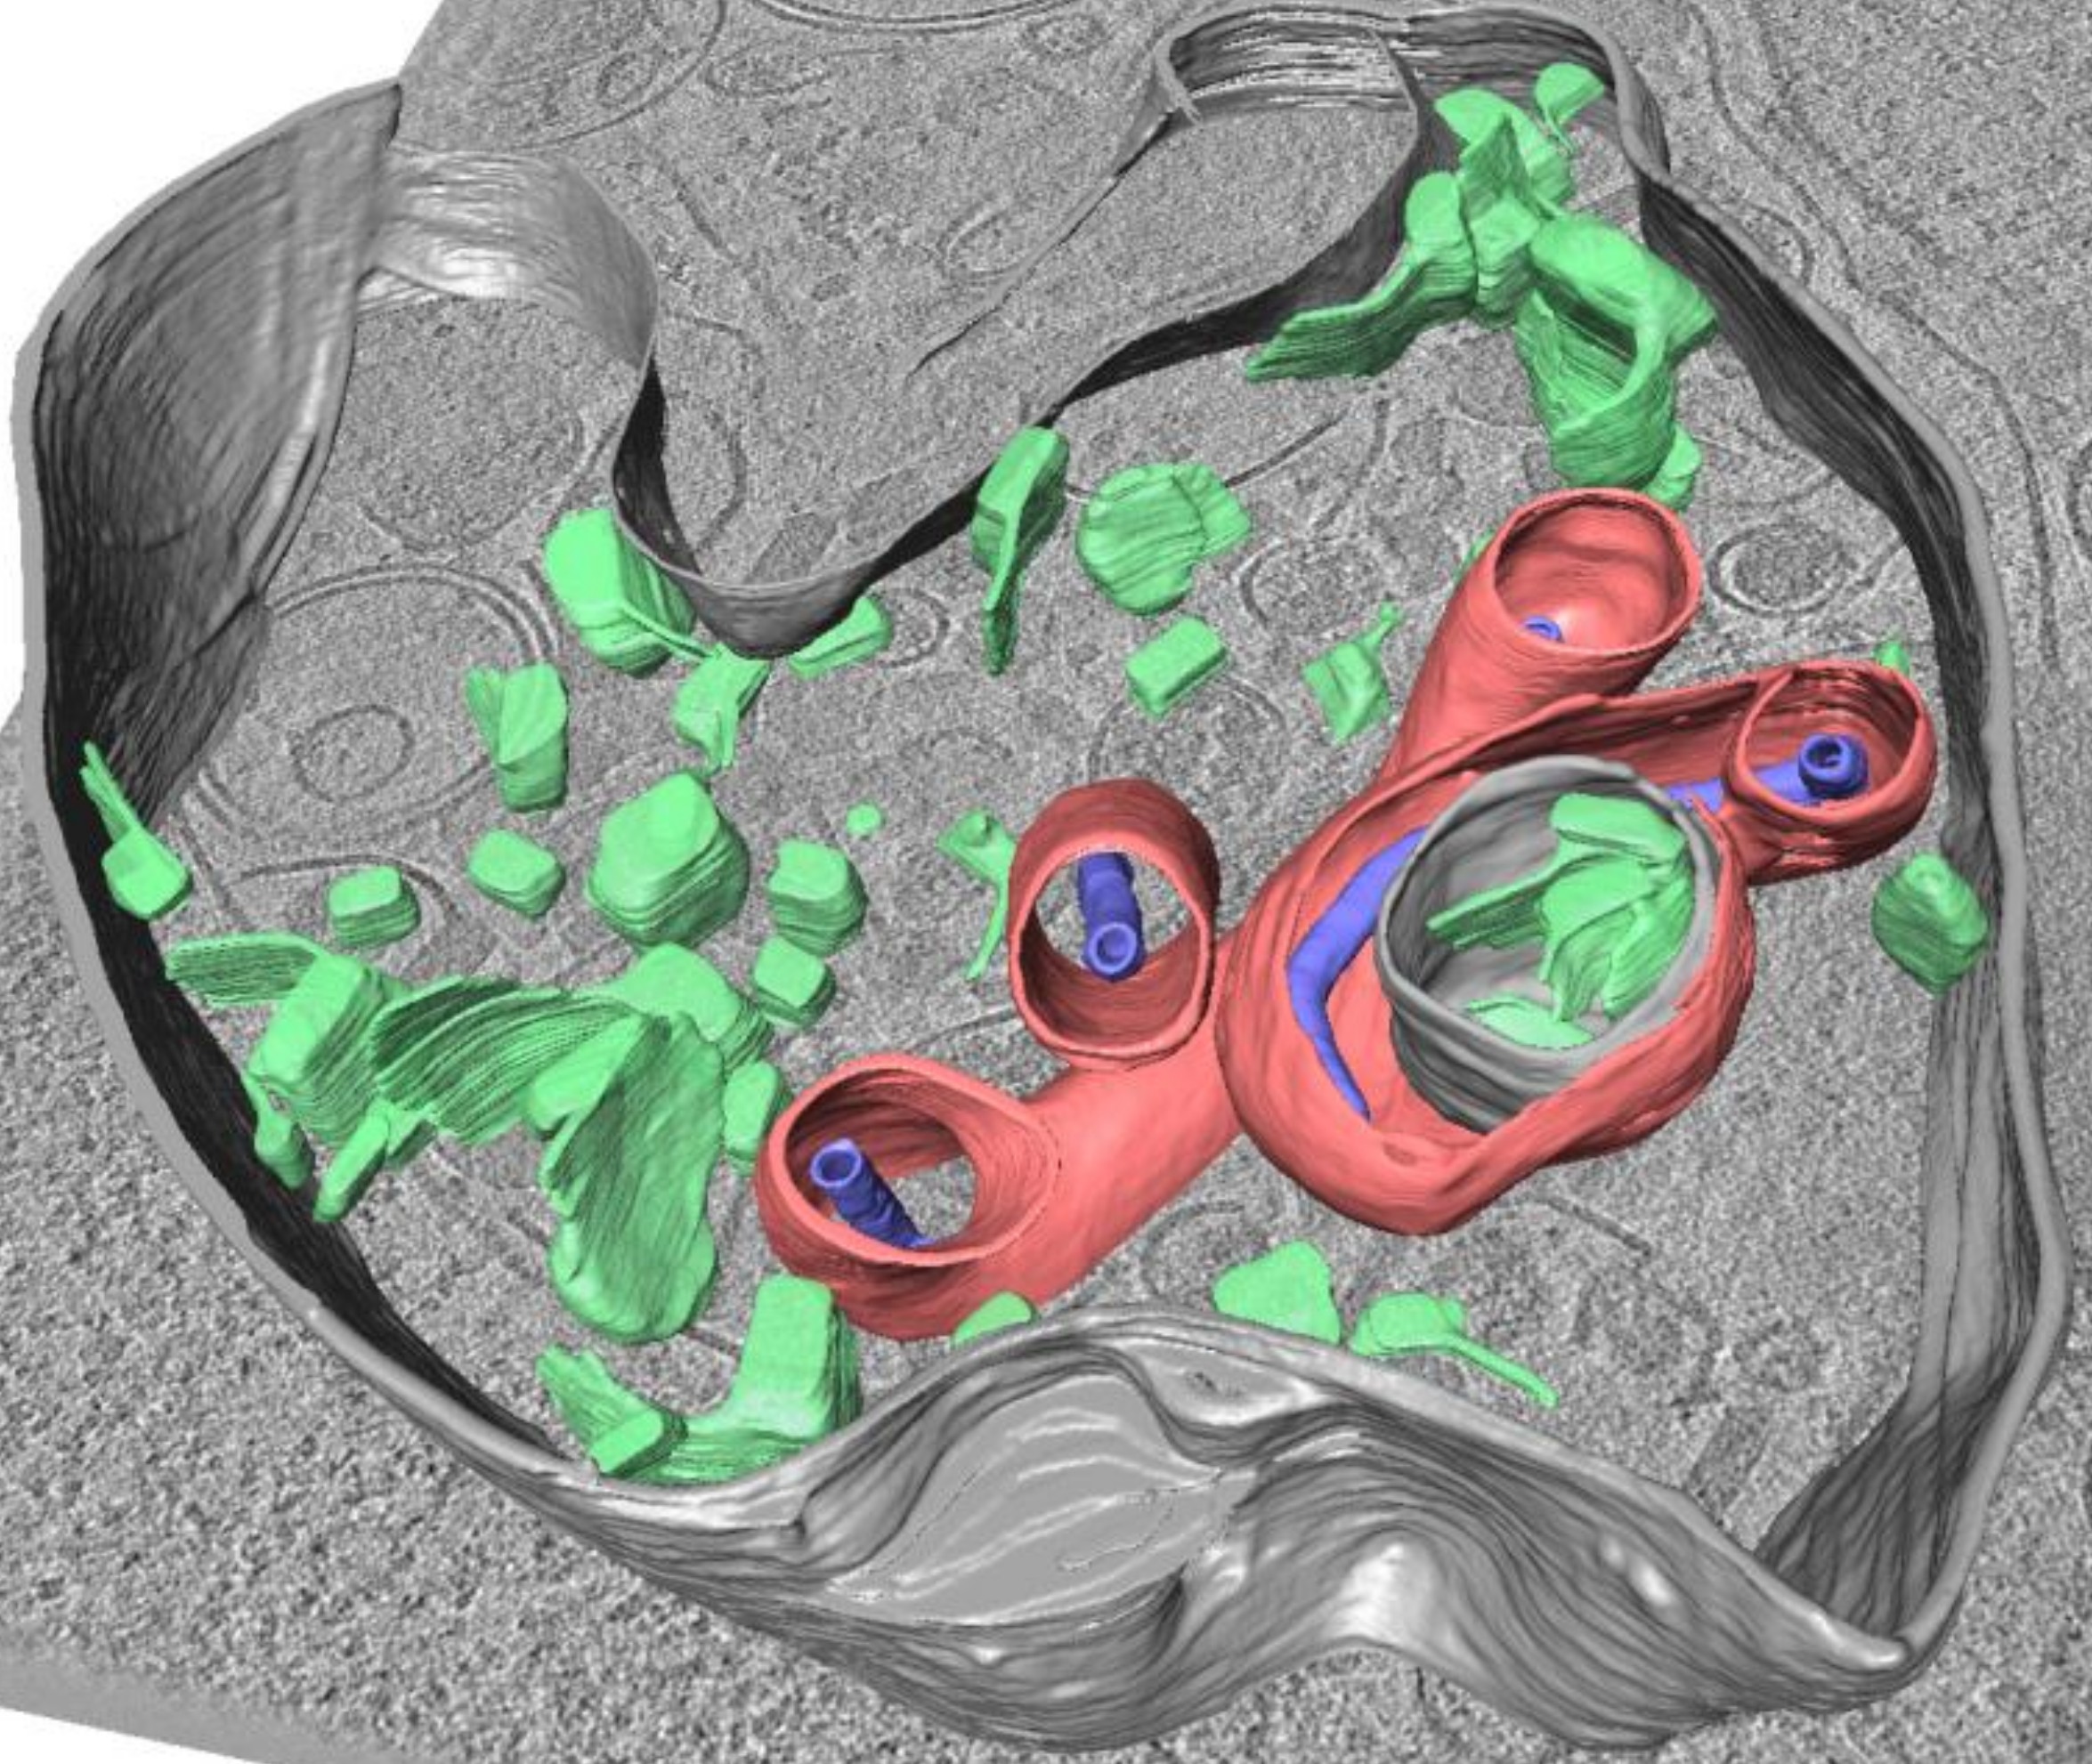

BioQuant Researchers from Chlanda and Schwarz Lab elucidate mechanisms that contribute to the prevention of Influenza A and Ebola virus infections. Cell Host & Microbe 31:1-18 (31 March 2023) EMBO Journal e113578 (21 April 2023)

Researchers from the BioQuant Groups of Petr Chlanda and Ulrich Schwarz, together with collaborators from both Heidelberg University and Heidelberg University Hospital, recently published their findings shedding light on Influenza A and Evola Virus entry into host cells.